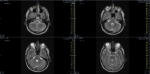

Das ist ja ganz toll, dass Ihr die Seite so schnell gefunden habt. Ich zeige euch jetzt ein ganz, ganz anderes Paßfoto von mir. Es könnte Ähnlichkeiten zu anderen lebenden oder bereits verstorbenen Personen geben. Wenn Ihr das erste Bild oben links anklickt wird es ver- größert dargestellt. Dann kann man mit den Pfeiltasten am unteren Bild- rand durch meinen Kopf blättern. Es gibt nicht viel zu sehen. Vielen Dank an Martina für Ihre Hilfe.

MRT